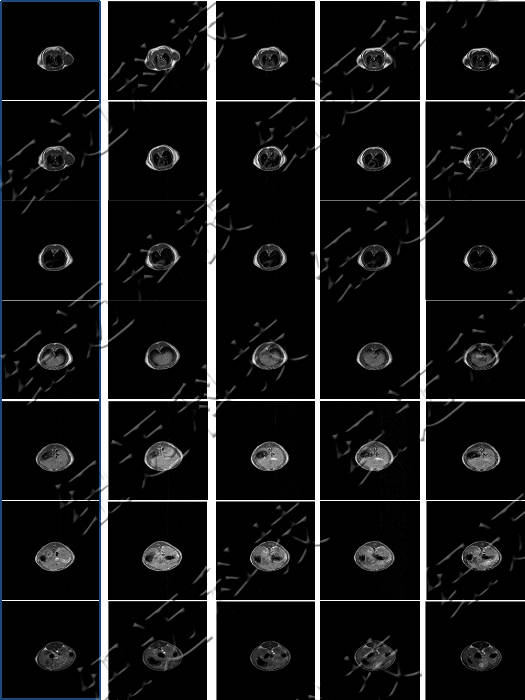

大鼠体内造影剂代谢MRI横断面

仪器使用小动物核磁共振成像系统,图像为T1加权像横断面、冠状面,采样参数如下:FOV=100mm×100mm, TR=400ms, TE=19ms, 层厚3.5mm, 层间距1mm, 累加次数16, K空间大小192×256。成像结果显示,注射造影剂后,大鼠心脏与肝脏变亮,且随代谢时间延长逐渐变暗。